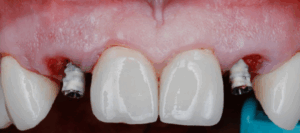

Since temp shells were already fabricated, we were ready to pick up our temporary prosthesis using non-engaging temporary abutments.

When picking up a multiple unit bridge on temporary abutments, make sure to never use flowable due to possible shrinkage of the material and only use self-curing no-shrinkage resin based material (Integrity).

Once the temporary is picked up and emergence profile is customized to have an adequate regenerative space and properly placed Critical contour (0.5 short of the final gingival margin) we are ready to deliver the prosthesis.

Prior to delivery make sure to leave a good amount of room in the embrasures to allow for soft tissue fill during the training period.